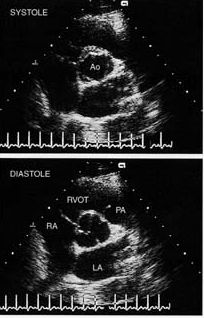

超声心动图

超声心动图切面

超声心动图标准切面

二维超声心动图